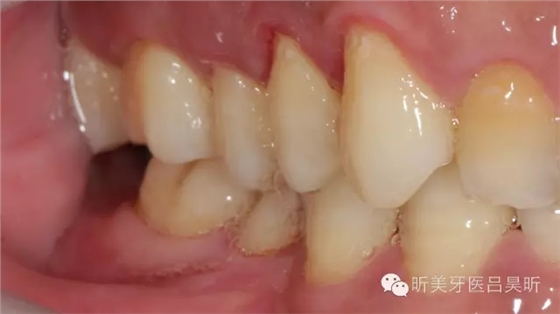

術(shù)前口內(nèi)檢查,可見牙槽骨寬度良好,角化齦量適中